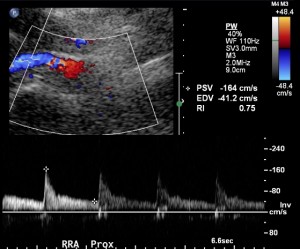

The next step is to identify the renal arteries. Each renal artery should be sampled in its origin and proximal, mid and distal portions. The distal portion of the renal artery is often difficult to obtain from the midline even in easy renal artery ultrasound. The proximal portion is difficult to obtain from the flank and therefore effort should be made to obtain it from the midline.

Sometimes the images are less than optimal. If there is uncertainty, images should not be acquired. However, if the renal artery can be identified coming in from the rest of the noise, then it can be sampled:

The flank approach as part of a renal artery ultrasound allows for imaging of the kidneys and blood flow in them. It also allows to circumvent bowel gas and sometimes visualize the renal arteries better. The flank approach is practical for visualizing the mid and distal renal arteries, more than the proximal renal artery.

The last, but perhaps most important, part of performing the renal artery ultrasound from the flank approach is to sample the renal artery. The goal of the ultrasonographer is to elongate as much as the renal artery from the hilum to the aorta. If the full length of the renal artery is identified, then velocity sampling can be performed with confidence. Otherwise, there is an element of guessing.

Sampling from the renal artery should be performed with angle correction.

A high-quality renal artery ultrasound will repeat similar measurements from both the midline and the flank approach. If there is great discrepancy between these measurements, it may mean that one of them is wrong.